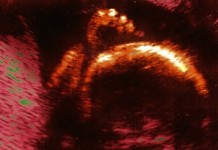

Будущий ребенок Ребенок уже чувствует ваши перемещения в пространстве. Он почувствует, если вы начнете танцевать. Малыш весит 450-500 г. Теперь вы не только ощущаете его...

Будущий ребенок Длина тела малыша – уже 9,5 – 10 см от макушки до копчика. Ваш малыш размером с яблоко. Плод активно пропускает через себя...

Будущий ребенок Будьте готовы: малыш начнет расти не по дням, а по часам. В ближайшие две недели он прибавит в весе в 2 раза. Сейчас...